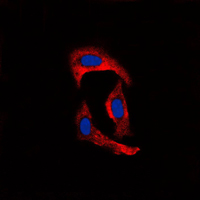

Immunofluorescent analysis of MMP1 staining in MCF7 cells. Formalin-fixed cells were permeabilized with 0.1% Triton X-100 in TBS for 5-10 minutes and blocked with 3% BSA-PBS for 30 minutes at room temperature. Cells were probed with the primary antibody in 3% BSA-PBS and incubated overnight at 4 °C in a humidified chamber. Cells were washed with PBST and incubated with a DyLight 594-conjugated secondary antibody (red) in PBS at room temperature in the dark. DAPI was used to stain the cell nuclei (blue).